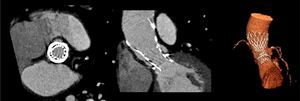

The patient was referred for aortic valve replacement surgery, but was refused on medical and surgical evaluation due to the high surgical risk (logistic EuroSCORE 22.3%). Percutaneous treatment was then considered, and anatomical assessment by transesophageal echocardiography and multidetector computed tomography showed this to be technically feasible. In particular, there was no significant iliofemoral arterial disease that would hinder access (Figure 2).

A 26-mm Medtronic CoreValve prosthesis was implanted under general anesthesia via femoral access. The prosthesis was released under rapid pacing for greater control and precision during implantation, the device being positioned higher than is usual for native valves given the smaller diameter of the underlying prosthetic ring. The final angiographic result was excellent, with minimal perivalvular regurgitation (Figure 3).